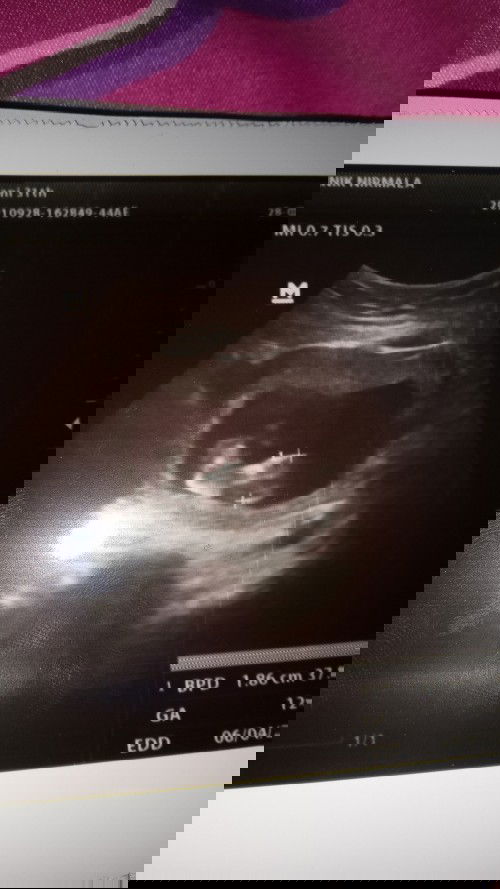

Lihat beby